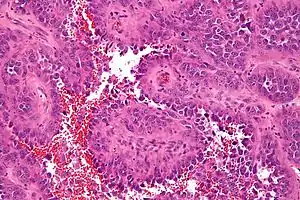

| Micrograph of an angiosarcoma. H&E stain. | |

Angiosarcomas show signs of hemorrhage and necrosis. Pathologically, tumor cells show increased nuclear to cytoplasm ratio, nuclear hyperchromasia, nuclear pleomorphism and high mitotic activity.[1]